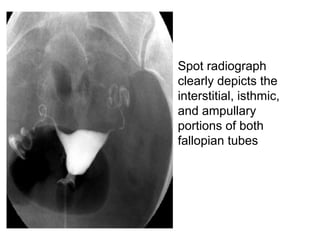

• Spot radiograph

clearly depicts the

interstitial, isthmic,

and ampullary

portions of both

fallopian tubes

• Spot radiograph clearlydepicts the interstitial, isthmic, and ampullary portions of both fallopian tubes